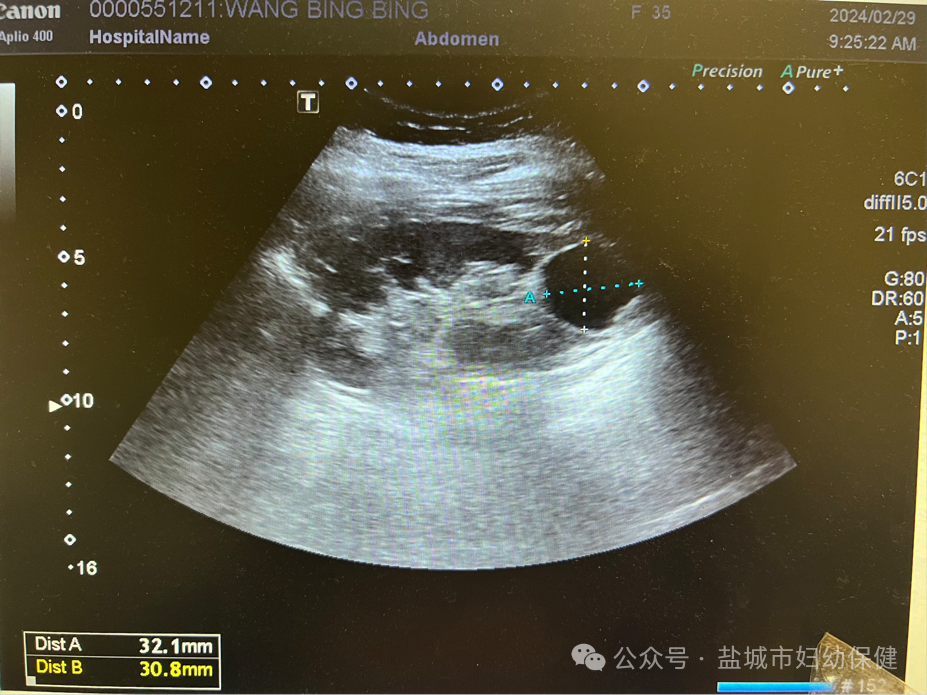

肾囊肿是指肾脏内出现大小不等的、与外界不相通的囊性包块,囊内充有透明液体。超声仪器一般能显示大于5mm的肾囊肿。单纯性的肾囊肿最为常见,超声的表现是呈圆形或椭圆形的无回声区。囊壁薄而光滑,后方回声增强,内部没有血流信号。囊肿常向肾表面突出,其大小不一。

但是,需要注意的是,当囊肿出现并发症时超声可表现为有分隔、囊壁增厚、透声差等复杂性囊肿的超声表现,超声一旦发现肾脏的囊性病灶有厚壁分隔、壁结节,应高度警惕囊性肾癌的可能性。